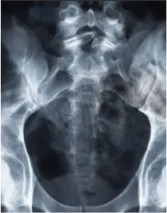

Остеопороз — это системное заболевание скелета, которое характеризуется потерей общей костной массы, в связи с чем, кости становятся хрупкими и ломаются даже при небольших нагрузках.

Из-за остеопороза возможны переломы костей бедра, предплечья, а также позвонков в спине.